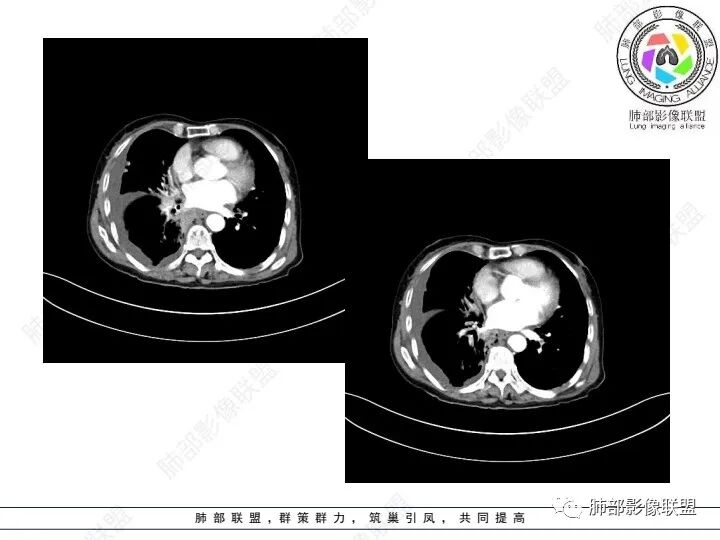

右肺下叶类圆形软组织密度影,纵隔及肺门多发肿大淋巴结、有融合,右下肺支气管壁增厚伴环形钙化、狭窄,右侧胸膜见结节灶,增强后均匀明显强化;右侧胸腔积液。考虑:右肺下叶肿瘤伴纵隔肺门、胸膜转移,考虑腺癌可能。

老年女性,右肺下叶后基底段实性肿块,边缘强化明显,坏死,形态湖泊状,坏死轮廓不清,右肺门下方淋巴结肿大融合,包绕右肺下叶支气管血管束开口,右肺脏层及叶间胸膜多发转移强化结节,右侧胸腔积液,肺气肿背景,支持恶性,肺腺Ca,右肺下叶肿块经皮肺穿刺活检,另消化道岀血,Ca125值明里高,与肠Ca,补充腹部CT平扫及增强和肠镜检查,肠Ca右肺转移待排。

女,69,腹痛、便血4小时。CA125增高。胸部CT:肺气肿背景。右下叶不规则肿块影,处于外周气肿带与正常肺交界区,强化不均匀,中心有坏死;纵隔及肺门多发肿大淋巴结、融合,包绕支气管,部分钙化、环形强化;右下支气管周围管壁增厚伴环形钙化、狭窄。右侧胸膜多发结节灶,增强后明显强化,右侧胸腔积液。考虑恶性,右下肺腺Ca多发转移?转移瘤?鉴别TB、IgG4等。

3、胸部增强CT示右肺下叶脊柱旁不规则软组织肿块,侵及壁层胸膜外,密度不均匀,不均匀强化,中心低密区可疑坏死,右侧胸腔积液、胸膜结节影或结节样增厚,增强扫描可见强化,右侧肺门及纵隔内可见淋巴结肿大、融合,右侧中尖段支气管及右肺下叶支气管受侵,管腔狭窄。

4、综上,老年男性,CA125升高,右肺下叶肿块侵犯胸壁,伴纵隔、右肺门及纵隔淋巴结肿大,右侧胸腔积液、胸膜增厚伴结节影,强化明显,应该为一较典型的肺癌伴肺胸膜腔及肺门纵隔淋巴结转移,尤其是肺腺癌。

几个细节值得留意:

1)由肺内侵及胸壁的块影,即提示其恶性生物学行为,也不为转移灶所常见。

2)右肺下叶肿块,右肺门及纵膈未见肿大淋巴结,符合肺癌迁徙途径。

3)转移瘤较少直接侵犯支气管。不是没有,如肾透明细胞癌转移或晚期无差别攻击,但总体较少。

4)转移灶多发但均限于右侧胸腔内,一般不符合远道而来的“双侧”。无论该患者有无腹腔或其他部位原发病灶。